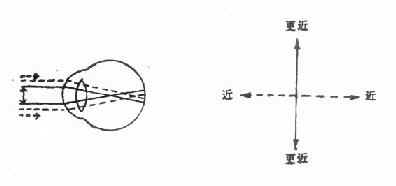

2.复性散光:两条主经线的屈光力不同,且都是远视性的(复性远视散光)或近视性的(复性近视散光)。

图16-11 复性近视散光